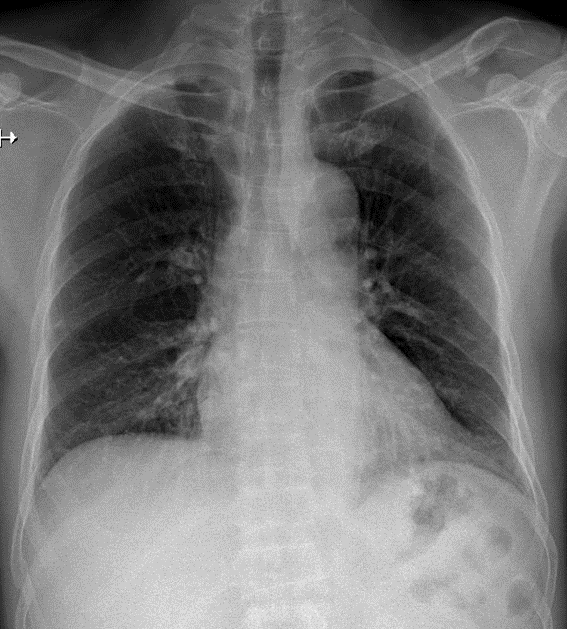

Hãy phân tích tình huống

1-Gãy 1/3 ngoài xương đòn (T) kèm di lệch nhẹ